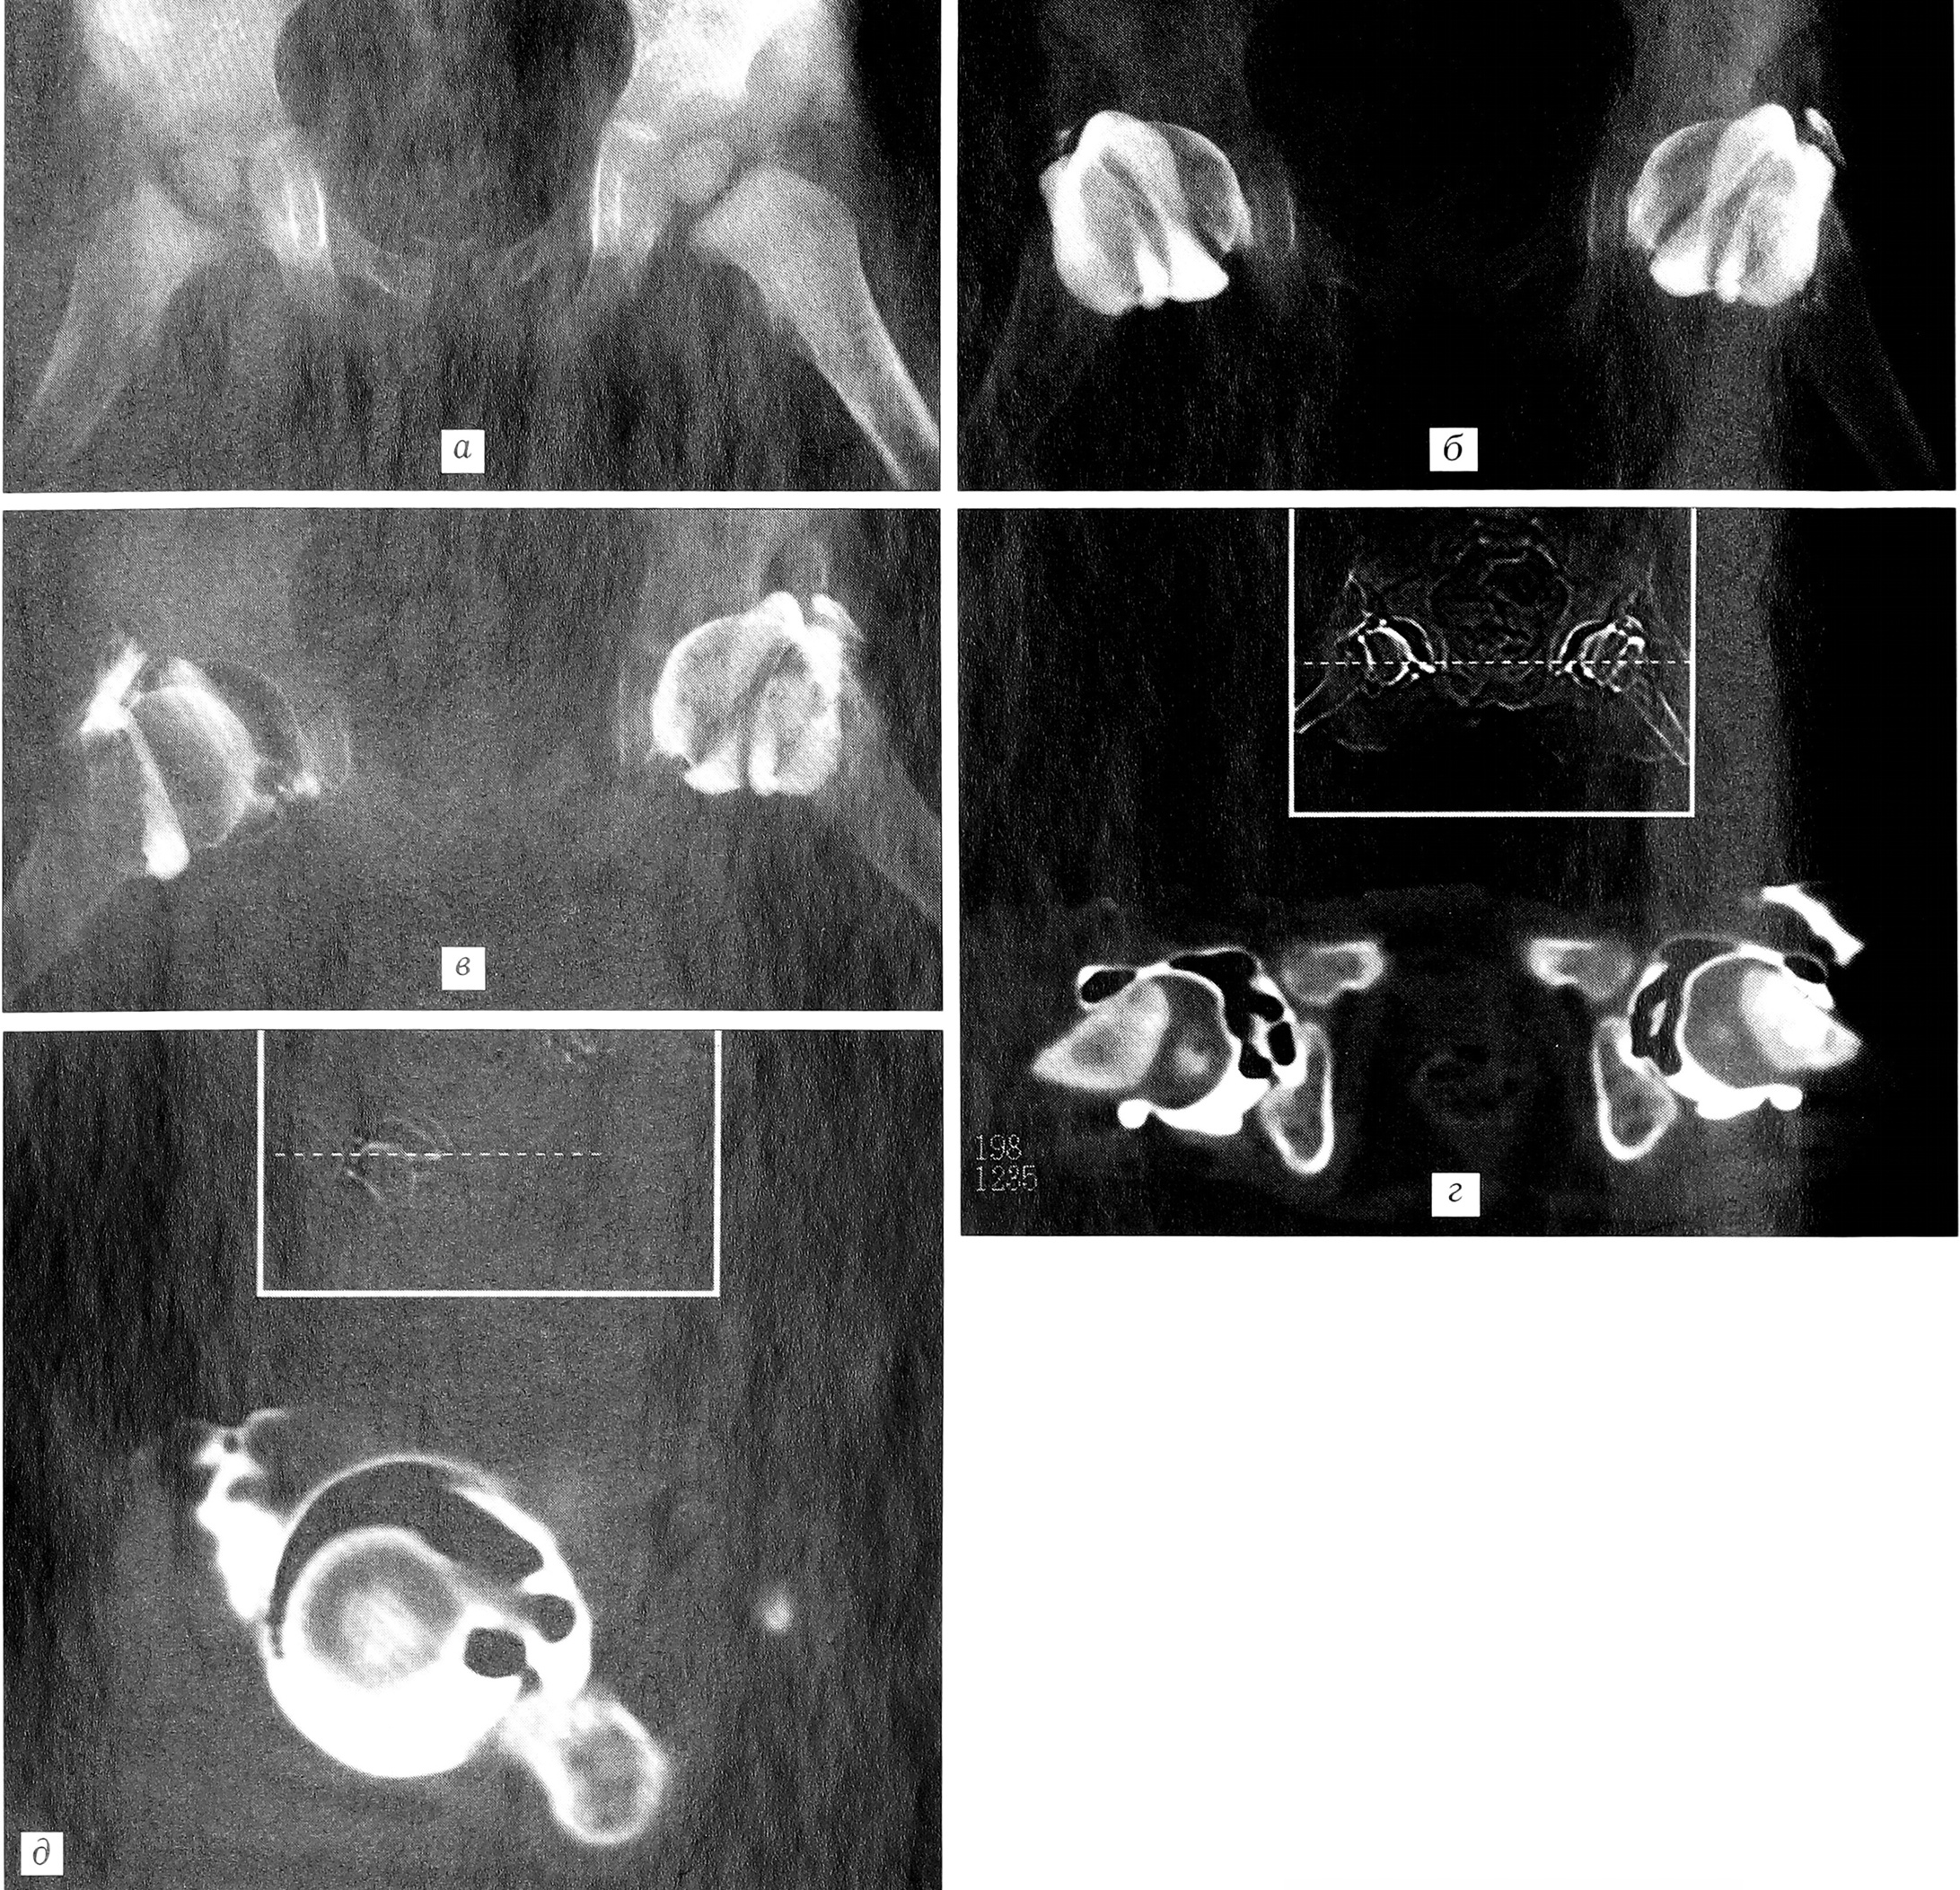

Поскольку у детей значительные отделы тазобедренного сустава выполнены хрящевой тканью, которая проницаема для рентгеновских лучей, имеется грубое несоответствие между анатомической картиной и данными лучевых методов исследования (рис. б, а). В связи с этим для визуализации хрящевых и внутрисуставных структур, а также капсульно-связочного аппарата сустава мы использовали различные методики контрастирования ТБС.

При артрографии с тугим заполнением полости сустава контрастным веществом хорошо визуализируются хрящевая часть крыши и верхний отдел ацетабулярной губы, а также все наружные завороты сустава, такие как recessus colli, recessus supraorbicularis и infraorbicularis (рис. 6, б). Однако при этом хрящевая поверхность головки бедренной кости определяется не совсем отчетливо. Компьютерная томография с использованием данной методики контрастирования позволяет визуализировать передний и задний отделы хрящевых краев вертлужной впадины и лимбуса, хрящевую часть головки бедренной кости. Однако при тугом заполнении полости сустава контрастным веществом возникает эффект затемнения хрящевых структур, и размеры головки, определяемые с помощью компьютерного томографа, оказываются на 20% меньше истинных.

Контрастирование полости ТБС кислородом также позволяет хорошо визуализировать суставные поверхности вертлужной впадины и головки бедренной кости, завороты полости сустава, но при этом плохо контурируются такие внутрисуставные структуры, как собственная связка головки бедра.

Методика двойного контрастирования является наиболее информативной как при артрографии, так и при компьютерной томографии, поскольку при данной методике головка бедра отходит от вертлужной впадины на 4-8 мм, что позволяет хорошо визуализировать суставные поверхности, лимбус, суставную капсулу, жировую подушку и собственную связку головки бедра (рис. 6, в). Последняя при рентгенографии в прямой проекции определяется в виде контурированного тяжа между ямкой головки бедренной кости и вырезкой вертлужной впадины, проходящего практически параллельно плоскости входа в вертлужную впадину и расширяющегося книзу. При компьютерной томографии на горизонтальных срезах собственная связка головки бедра выявляется как овоидное образование, располагающееся между головкой бедра и вертлужной впадиной в передненижнем отделе сустава (рис. 6, г). Использование при КТ косой укладки, когда плоскость срезов проходит параллельно плоскости входа в вертлужную впадину, позволяет визуализировать собственную связку головки бедра на всем протяжении от ямки головки до вырезки вертлужной впадины (рис. 6, б). Такую же возможность дает мультипланарная реконструкция изображения при стандартной методике исследования.

Рис. 6. Тазобедренный сустав ребенка 1,5 лет.a — обзорная рентгенограмма; б — артрограмма; в — артропневмограмма: хорошо визуализируется собственная связка головки бедра; г — компьютерная томограмма, аксиальный срез; д — компьютерная томограмма, косой срез.